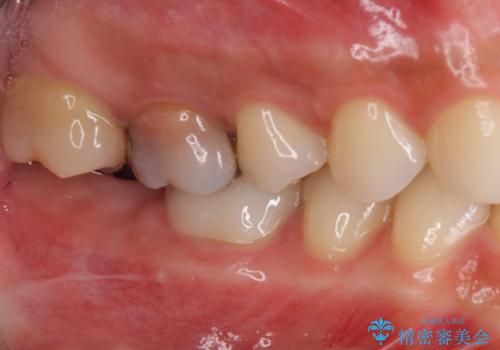

歯茎が腫れる インプラントでの治療

- 40代女性

- 10ヶ月

- 5-10回

- 左上5/インプラント:242,000円 骨増生:55,000円 カスタムアバットメント:110,000円 インプラント用仮歯:22,000円 ジルコニアクラウン:121,000円 合計550,000円費用は治療当時の料金となります